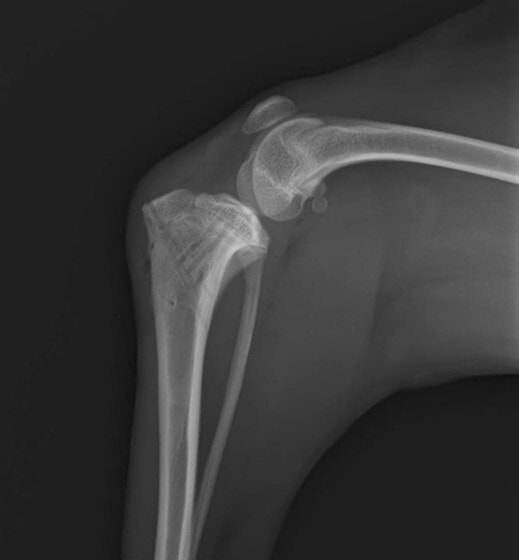

他院にて左大腿骨遠位の成長板骨折(salter-harrisⅠ型)が認められており、治療相談を目的として来院。当院にて、キルシュナーワイヤーを用いたピンニングにより骨折部位の整復を行いました。術後の経過は良好で、現在も経過観察中です。

術後レントゲン

機器

Arthrex社のターゲティングデバイスを用いてピンニングの位置を調整することで、確実な固定を行っています。当院ではこの手術器具以外にも、人の手術にも使用される様々な器具を導入し、手術精度を高め、また医療メーカーと新しい器具の開発、試作にも取り組んでおります。